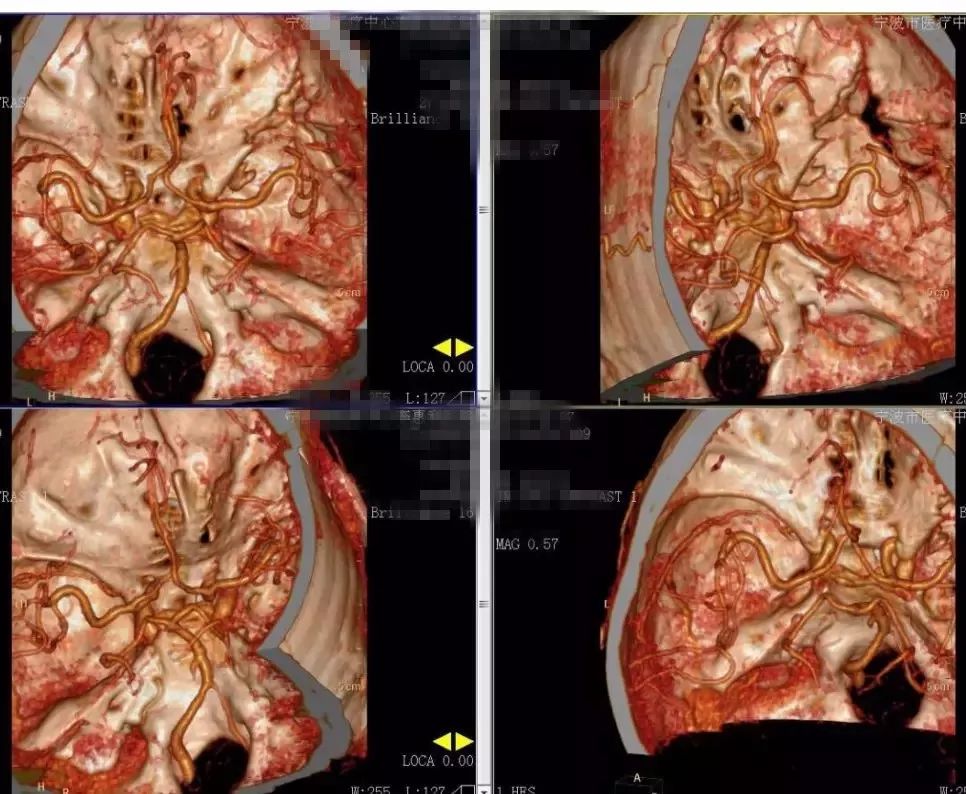

2018-2-13 CTA提示右颞部DAVF可能(图6),建议DSA。仔细阅片CTA未见明显引流静脉,考虑右侧脑膜中动脉假性动脉瘤可能更大。次日行 DSA检查,证实为“右侧脑膜中动脉假性动脉瘤”(图7)。当日即行“右侧翼点入路,脑膜中动脉假性动脉瘤切除加血肿清除术”(图8)。病理回报:镜下纤维细胞增生,可见血凝块伴机化(图9)。2018-2-27 复查CTA提示右侧脑膜中动脉假性动脉瘤术后改变,未见残余及复发(图10)。

图6. 2018-2-13 CTA提示右颞部DAVF可能。

图7. 2018-2-14 DSA提示右侧脑膜中动脉假性动脉瘤。

图10. 2018-2-27 复查CTA提示右侧脑膜中动脉假性动脉瘤术后改变,未见残余及复发。